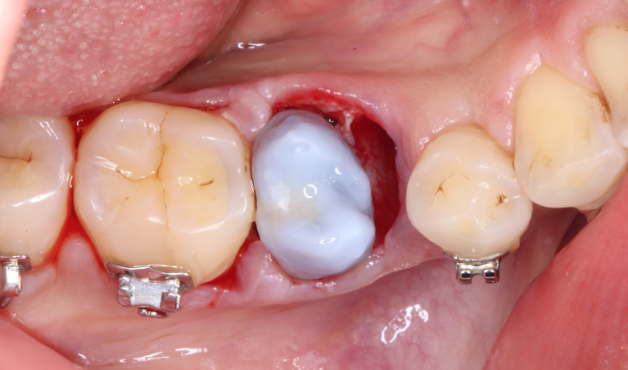

自家歯牙移植と根管治療で

天然歯を保存した症例

タップで写真の拡大ができます。

Before

Under Treatment

After

主訴

歯を残せないと言われた。インプラントは先延ばしにしたい

治療内容

自家歯牙移植 / イニシャルトリートメント(大臼歯)レジンコア

治療期間

2ヶ月

治療費用

308,000

治療の

リスク

術後しばらくしてから骨性癒着、外部吸収を起こす可能性があります。